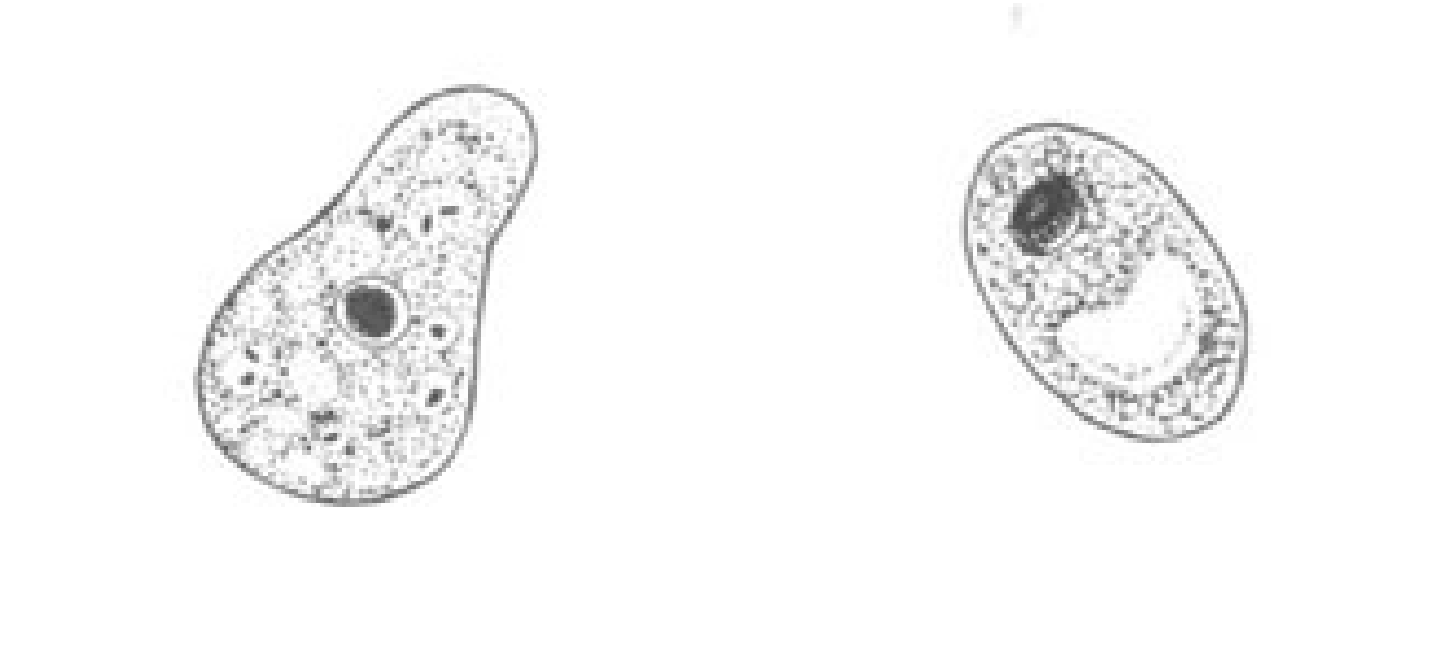

Naegleria fowleri

Naegleria fowleri

Naegleria fowleri cyst